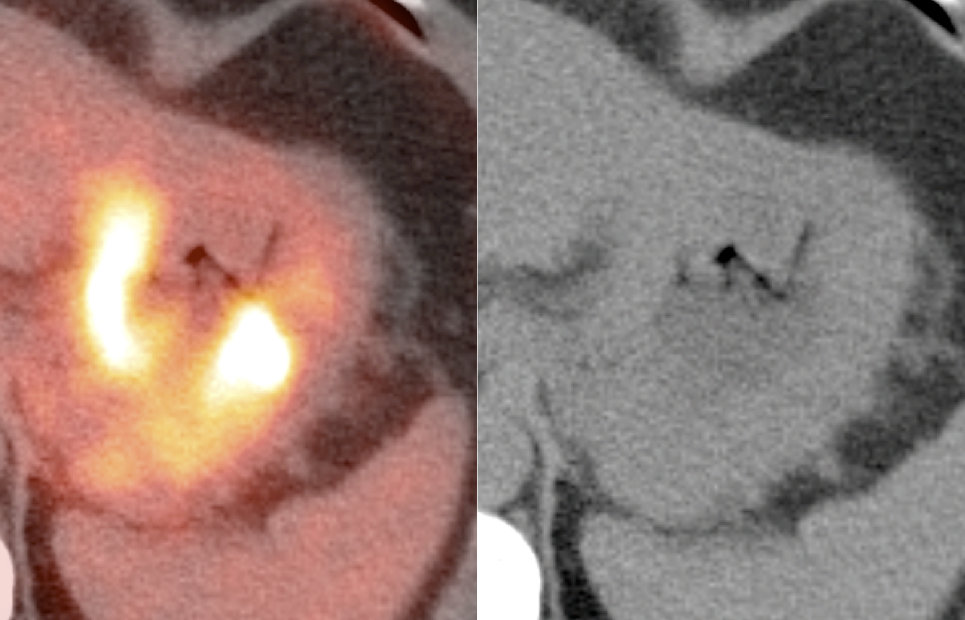

- Liver Ablation